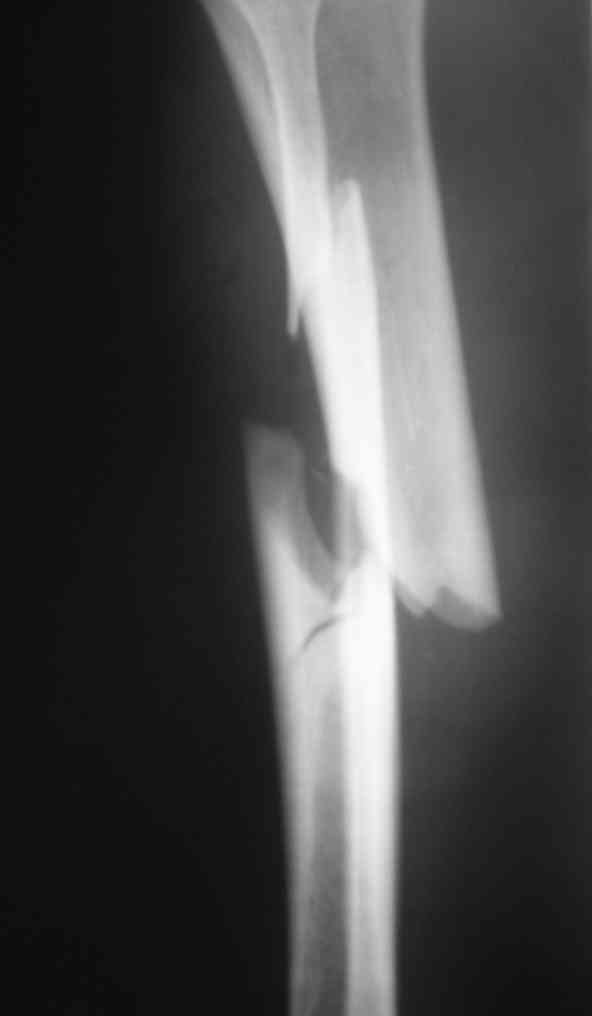

Дорогой Александр. Имею скромный опыт использования системы Fixion при переломах плеча, бедра и тибии. Всего 18 наблюдений с сентября 2006 г. Результаты отличные. Гвоздь индивидуален для каждого медуллярного канала. Легко имплантируется как в узкий, так и в деформированный канал. Это позволяет применять метод интрамедулярного остеосинтеза без ненужных потерь времени операции, флюороскопии и реально снижает крвопотерю и операционный риск. Удаление происходит без проблем. Особенно интересны больные с ипсилатеральными переломами бедра и голени.

> Особенно интересны больные с ипсилатеральными переломами бедра и голени.

Да, спасибо за интересные иллюстрации. Получилось очень симпатично. На большеберцовой кости непременно надо было винты? Там же был торцовый упор, перелом в средней трети?